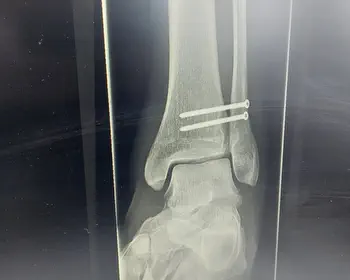

Aus der Kategorie, muss nicht sein, habe ich mir letzten den Fuß ordentlich lädiert. Der Arzt schickte mich zur Radiologie, hier wurde geröntgt und ein CT erstellt. Die Geräte waren von Siemens Healthineers, wohl dem der Aktien des Unternehmens hat.

Die Dateien, bzw. Inhalte werden nun angezeigt, auf der linken Seite können wir uns durch die einzelnen Aufnahmen durchklicken.

Beim Ct können wir den Play-Button drücken und so die Animation anschauen und an den Stellen stoppen und etwas erkennen oder nicht.